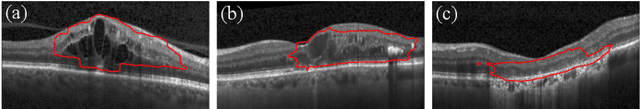

Abstract:Diagnosis and treatment guidance are aided by detecting relevant biomarkers in medical images. Although supervised deep learning can perform accurate segmentation of pathological areas, it is limited by requiring a-priori definitions of these regions, large-scale annotations, and a representative patient cohort in the training set. In contrast, anomaly detection is not limited to specific definitions of pathologies and allows for training on healthy samples without annotation. Anomalous regions can then serve as candidates for biomarker discovery. Knowledge about normal anatomical structure brings implicit information for detecting anomalies. We propose to take advantage of this property using bayesian deep learning, based on the assumption that epistemic uncertainties will correlate with anatomical deviations from a normal training set. A Bayesian U-Net is trained on a well-defined healthy environment using weak labels of healthy anatomy produced by existing methods. At test time, we capture epistemic uncertainty estimates of our model using Monte Carlo dropout. A novel post-processing technique is then applied to exploit these estimates and transfer their layered appearance to smooth blob-shaped segmentations of the anomalies. We experimentally validated this approach in retinal optical coherence tomography (OCT) images, using weak labels of retinal layers. Our method achieved a Dice index of 0.789 in an independent anomaly test set of age-related macular degeneration (AMD) cases. The resulting segmentations allowed very high accuracy for separating healthy and diseased cases with late wet AMD, dry geographic atrophy (GA), diabetic macular edema (DME) and retinal vein occlusion (RVO). Finally, we qualitatively observed that our approach can also detect other deviations in normal scans such as cut edge artifacts.

Abstract:The identification and quantification of markers in medical images is critical for diagnosis, prognosis, and disease management. Supervised machine learning enables the detection and exploitation of findings that are known a priori after annotation of training examples by experts. However, supervision does not scale well, due to the amount of necessary training examples, and the limitation of the marker vocabulary to known entities. In this proof-of-concept study, we propose unsupervised identification of anomalies as candidates for markers in retinal Optical Coherence Tomography (OCT) imaging data without a constraint to a priori definitions. We identify and categorize marker candidates occurring frequently in the data, and demonstrate that these markers show predictive value in the task of detecting disease. A careful qualitative analysis of the identified data driven markers reveals how their quantifiable occurrence aligns with our current understanding of disease course, in early- and late age-related macular degeneration (AMD) patients. A multi-scale deep denoising autoencoder is trained on healthy images, and a one-class support vector machine identifies anomalies in new data. Clustering in the anomalies identifies stable categories. Using these markers to classify healthy-, early AMD- and late AMD cases yields an accuracy of 81.40%. In a second binary classification experiment on a publicly available data set (healthy vs. intermediate AMD) the model achieves an area under the ROC curve of 0.944.